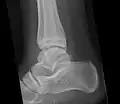

Ankle

Accessory bones at the ankle mainly include:

- Os subtibiale, with a prevalence of approximately 1%.[14] It is a secondary ossification center of the distal tibia that appears during the first year of life, and which in most people fuses with the shaft at approximately 15 years in females and approximately 17 years in males.[14]

- Os subfibulare, with a prevalence of approximately 0.2%.[15]

Os trigonum (further described below) may also be seen on an ankle X-ray.

The os trigonum or accessory talus represents a failure of fusion of the lateral tubercle of the posterior process of the talus bone. Is estimated to be present in 7–25% of adults.[17] It can be mistaken for an avulsion fracture of lateral tubercle of talus (Shepherd fracture) or a fracture of the Stieda process. In most cases, Os Trigonum will go unnoticed, but with some ankle injuries it can get trapped between the heel and ankle bones which irritates the surrounding structures, leading to Os Trigonum Syndrome.[21]